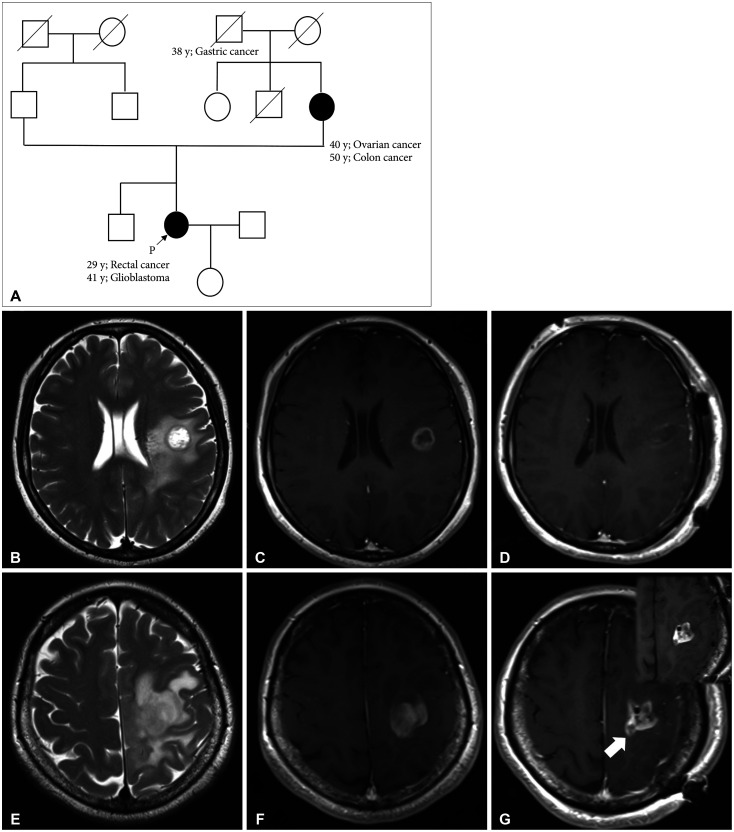

Lynch syndrome (LS) is an autosomal dominant disorder caused by mutations in mismatch repair (MMR) genes and is also known to be associated with glioblastomas. The efficacy of immunotherapy for LS-associated glioblastomas remains unknown. Herein, we report a rare case of LS-associated glioblastoma, treated with chemotherapy using immune checkpoint inhibitors (ICI). A 41-year-old female patient presented with headaches and sensory disturbances in the right upper limb for 6 weeks. She had been treated for rectal cancer and had a family history of LS. MRI revealed two ring-enhancing lesions in the left precentral gyrus. She underwent subtotal resection, leading to a pathological diagnosis of isocitrate dehydrogenase wild-type glioblastoma. She received daily administration of (temozolomide, 75 mg/m²) and concurrent radiotherapy (60 Gy) postoperatively. However, the tumor recurred 1 year after the initial treatment. A molecular genetic study showed high microsatellite instability (MSI), and she was treated with pembrolizumab therapy. Disease progression occurred despite six cycles of pembrolizumab therapy and radiotherapy at the dose of 40 Gy. She died due to glioblastoma progression 19 months after the initial treatment. The present case demonstrates that some LS-associated glioblastomas may be resistant to ICI despite high MSI, possibly because of intratumor heterogeneity related to MMR deficiency.